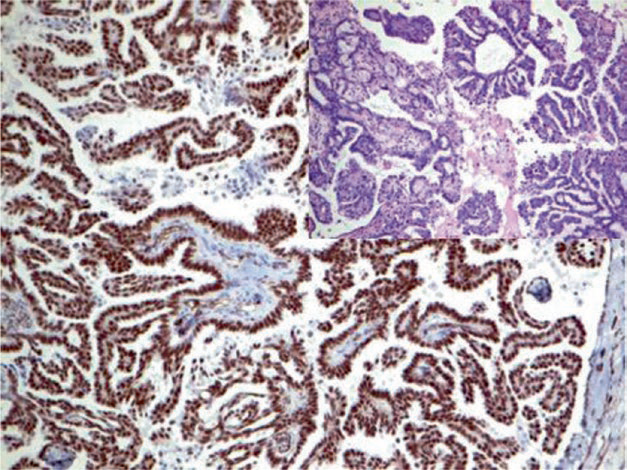

图1. 卵巢浆液性癌,免疫组化WT-1细胞核强阳性。

图2. 卵巢浆液性癌,免疫组化CA125细胞膜着色。